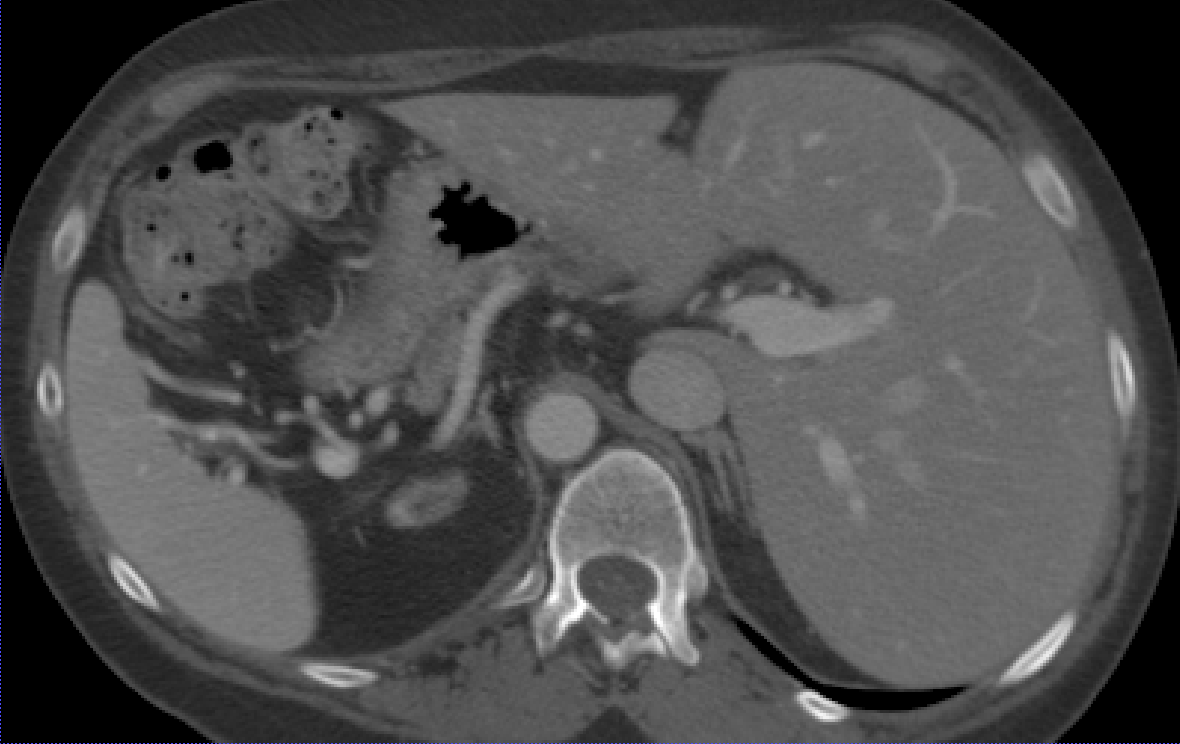

Specialized Organ Label Filter (SOLF). While automatic labeling enables creating large datasets, it introduces the possibility of noisy or erroneous labels. To mitigate this, we propose a filtration mechanism that removes outliers from segmentation. A question arises on how to distinguish segmentation failures from common patient abnormalities, e.g. enlarged liver. It’s important to note that human organs follow typical geometric properties that arise from the body’s need to optimize function while minimizing energy expenditure and structural stress. They reflect the underlying biological "blueprint" that has been honed by evolution [64]. inspired by the evolutionary regularity of human organs [64], we propose the Specialized Organ Label Filter (SOLF), using three features jointly: normalized volume, eccentricity, and sphericity (illustrated in Figure 3).

For each organ class , the normalized volume for some 3D sample is computed as where is the voxel count for the organ and is the total body voxel count. We define acceptable bounds for each feature by excluding the extreme percentiles. For example, the bounds for volume are set as

| (1) |

, where denotes the -th percentile function. Sphericity is defined as , with computed from voxel counts and as the surface area measured by counting the exposed voxel faces of the organ. Finally, eccentricity is defined as , where and are the smallest and largest eigenvalues of the covariance matrix of organ voxel coordinates. A sample is flagged as inaccurate if at least two of the three features (normalized volume, eccentricity, and sphericity) fall outside their respective acceptable ranges. Setting for SOLF effectively discards samples with anomalous organ characteristics while retaining valid labels. A single patient with abnormal organs is extremely unlikely to have more than a single independent aspect of deviation at the same time, hence indicating inaccurate labels.

We filter collected organ labels using the patient’s full-body statistics, a novel approach compared to previous methods that rely on flat label statistics (IQR) [10, 38] rather than patient meta-information and organ-specific features .